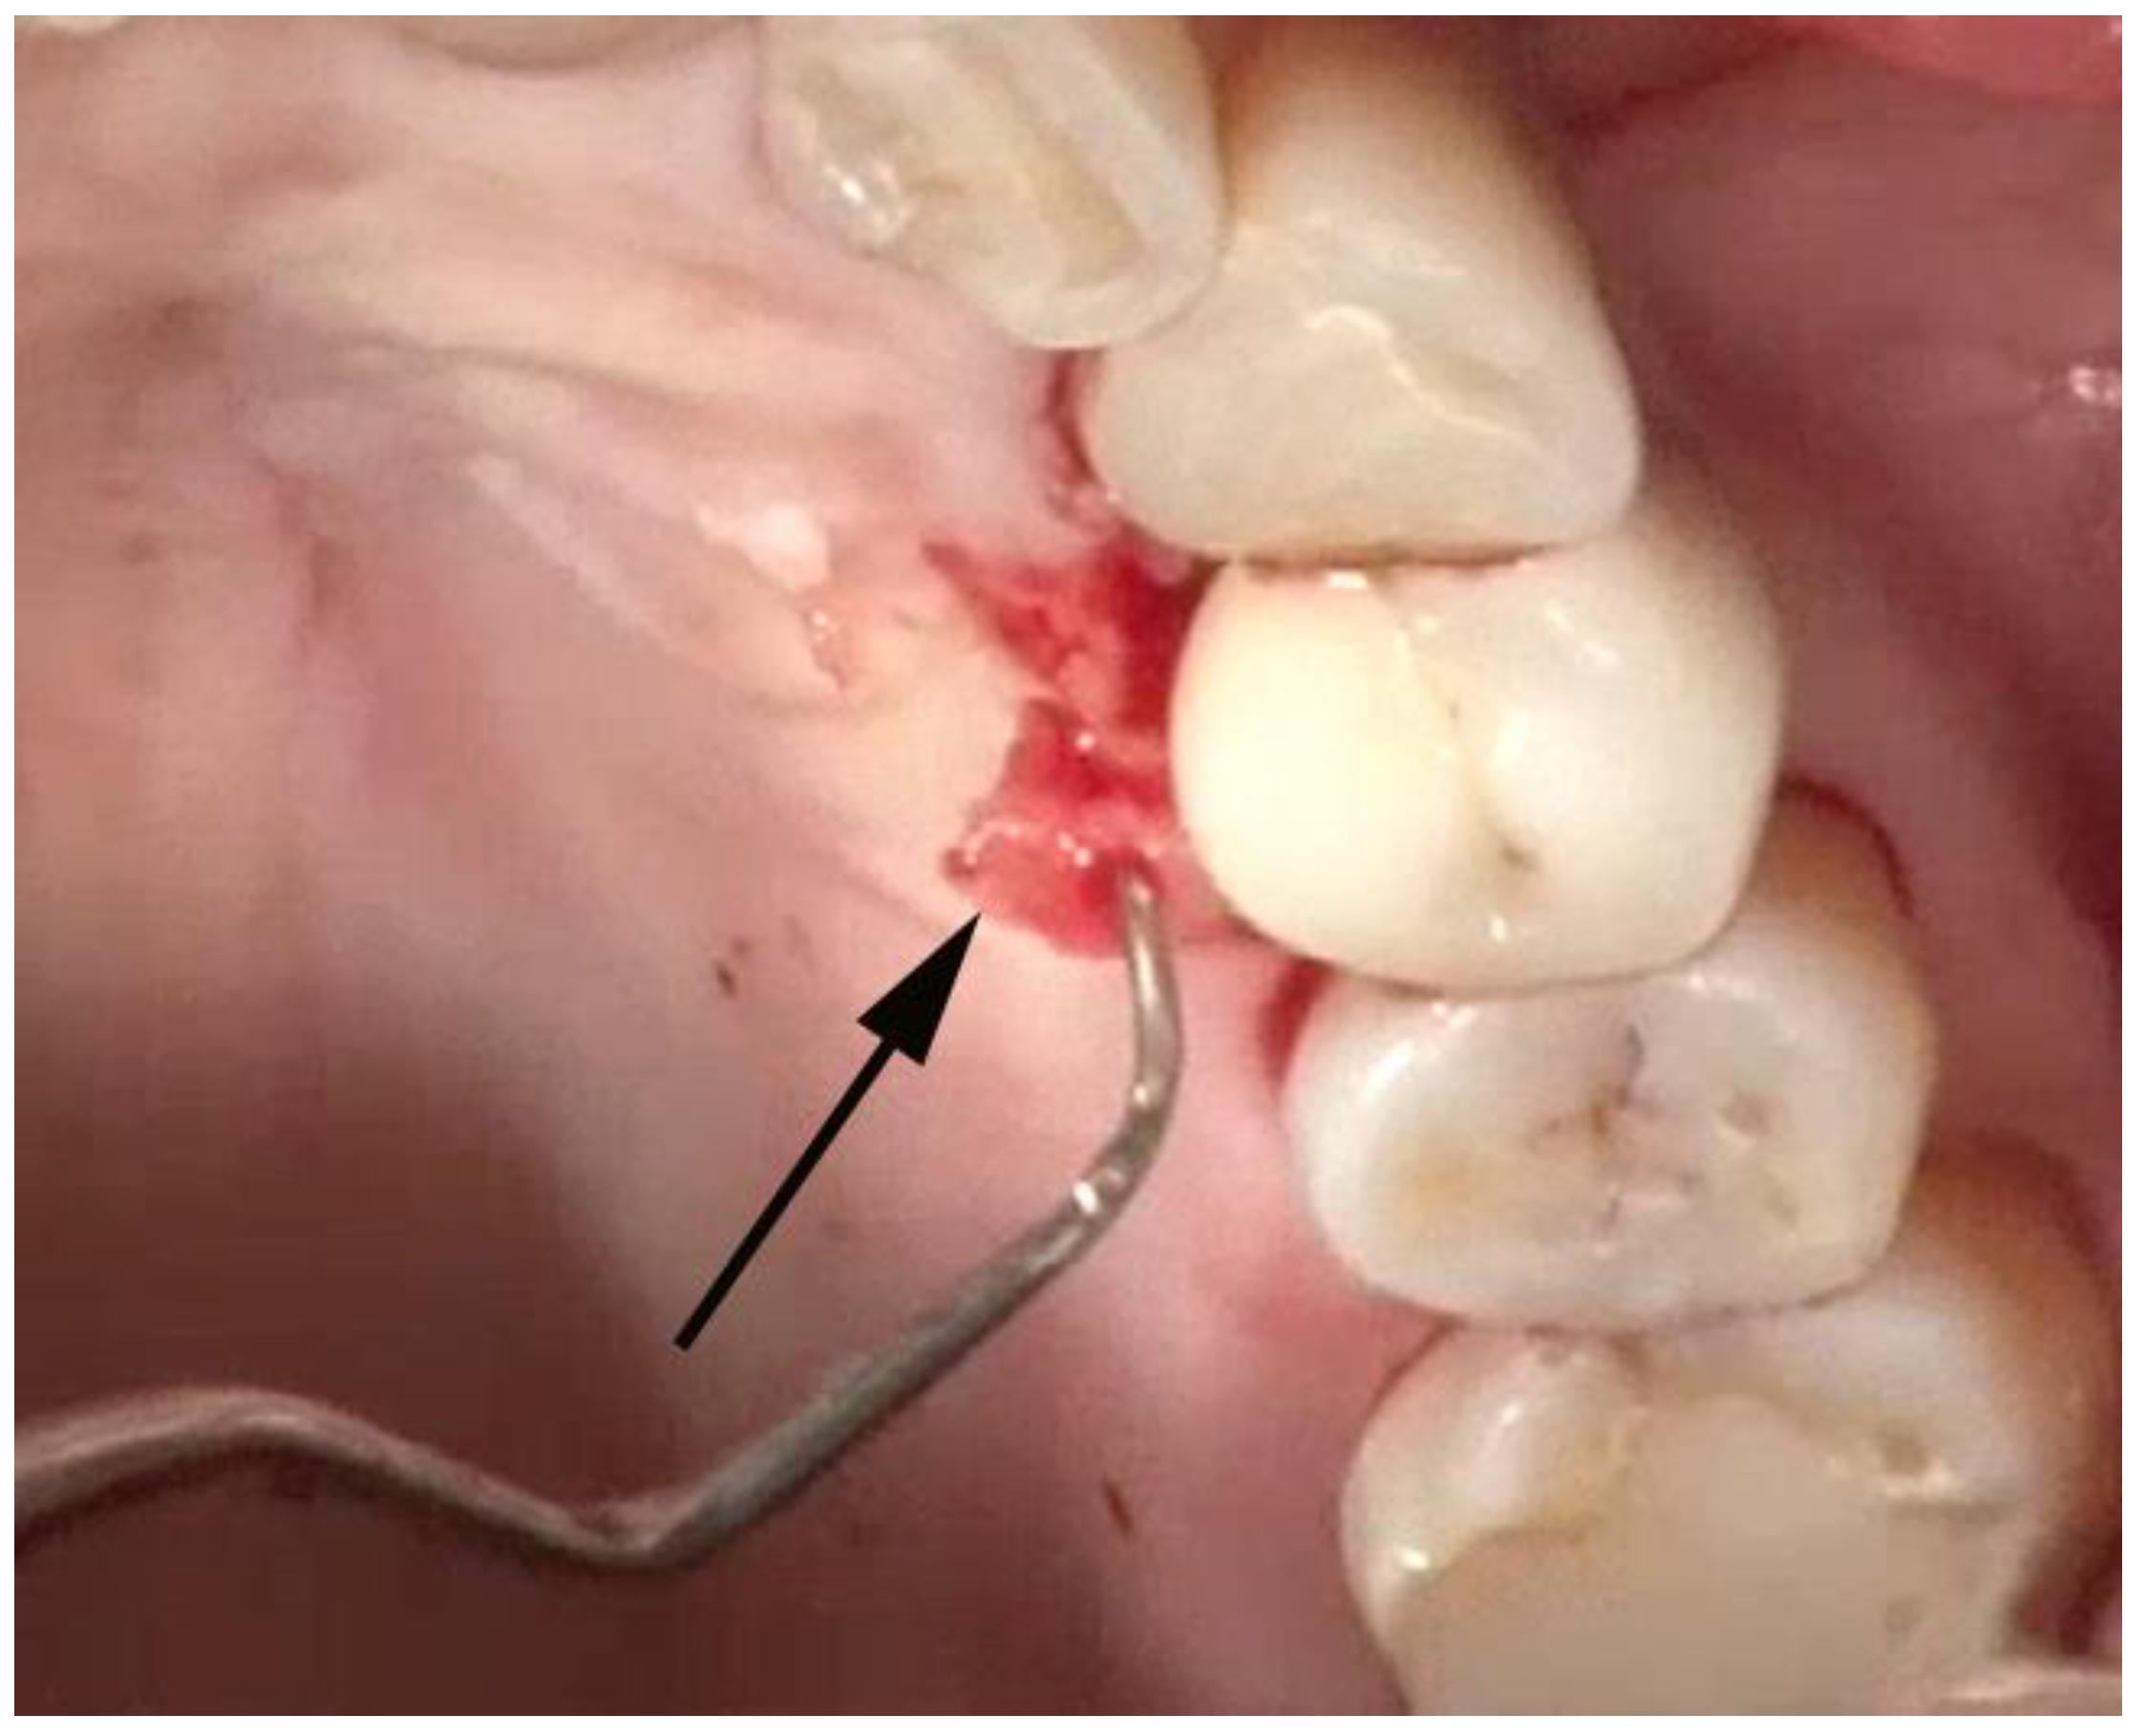

Incisions—The incisions for VMIS are limited to the area of bone loss. In most cases, the mesial-distal length of the incision is no more than 6–8 mm. With the availability of the videoscope, it is not necessary to use a longer incision to obtain visualization. The incisions are shown in Figure 2.

A sulcular incision (S in Figure 2) is made on the lingual aspect of the teeth on either side of the area of bone loss. When these incisions are made, the blade is placed against the root surface and inserted to the base of the defect. No tissue is removed with this incision. Unlike more traditional surgical approaches where the sulcus lining is removed or a “collar of tissue” is removed, the goal with VMIS incisions is to sever the granulation tissue only and to leave the rest of the tissue intact. Following the placement of the sulcular incisions, a connecting incision is made at the base of the papilla (P in Figure 2). This incision is made only to the crest of the bone. The goal is to retain as much of the periosteium on the bone as possible. Depending on the anatomy of the area, this may be the full extent of incisions that is necessary. If there is inadequate room to place the soft tissue retractor of the videoscope or if the bony defect cannot be adequately visualized, the papillary incision (P) can be extended apically as a split-thickness incision (Figure 3). Under no circumstance should a periosteal elevator be used to gain space. A periosteal elevator will pull the periosteium from the bone, which will greatly diminish the blood supply to the periodontal tissue. The use of a periosteal elevator is associated with a greater recession than that observed when a split-thickness approach is used.

Figure 3. The split-thickness incisions at the base of the papilla (P in Figure 2) are designed to leave the periosteium intact. A periosteal elevator should not be used.